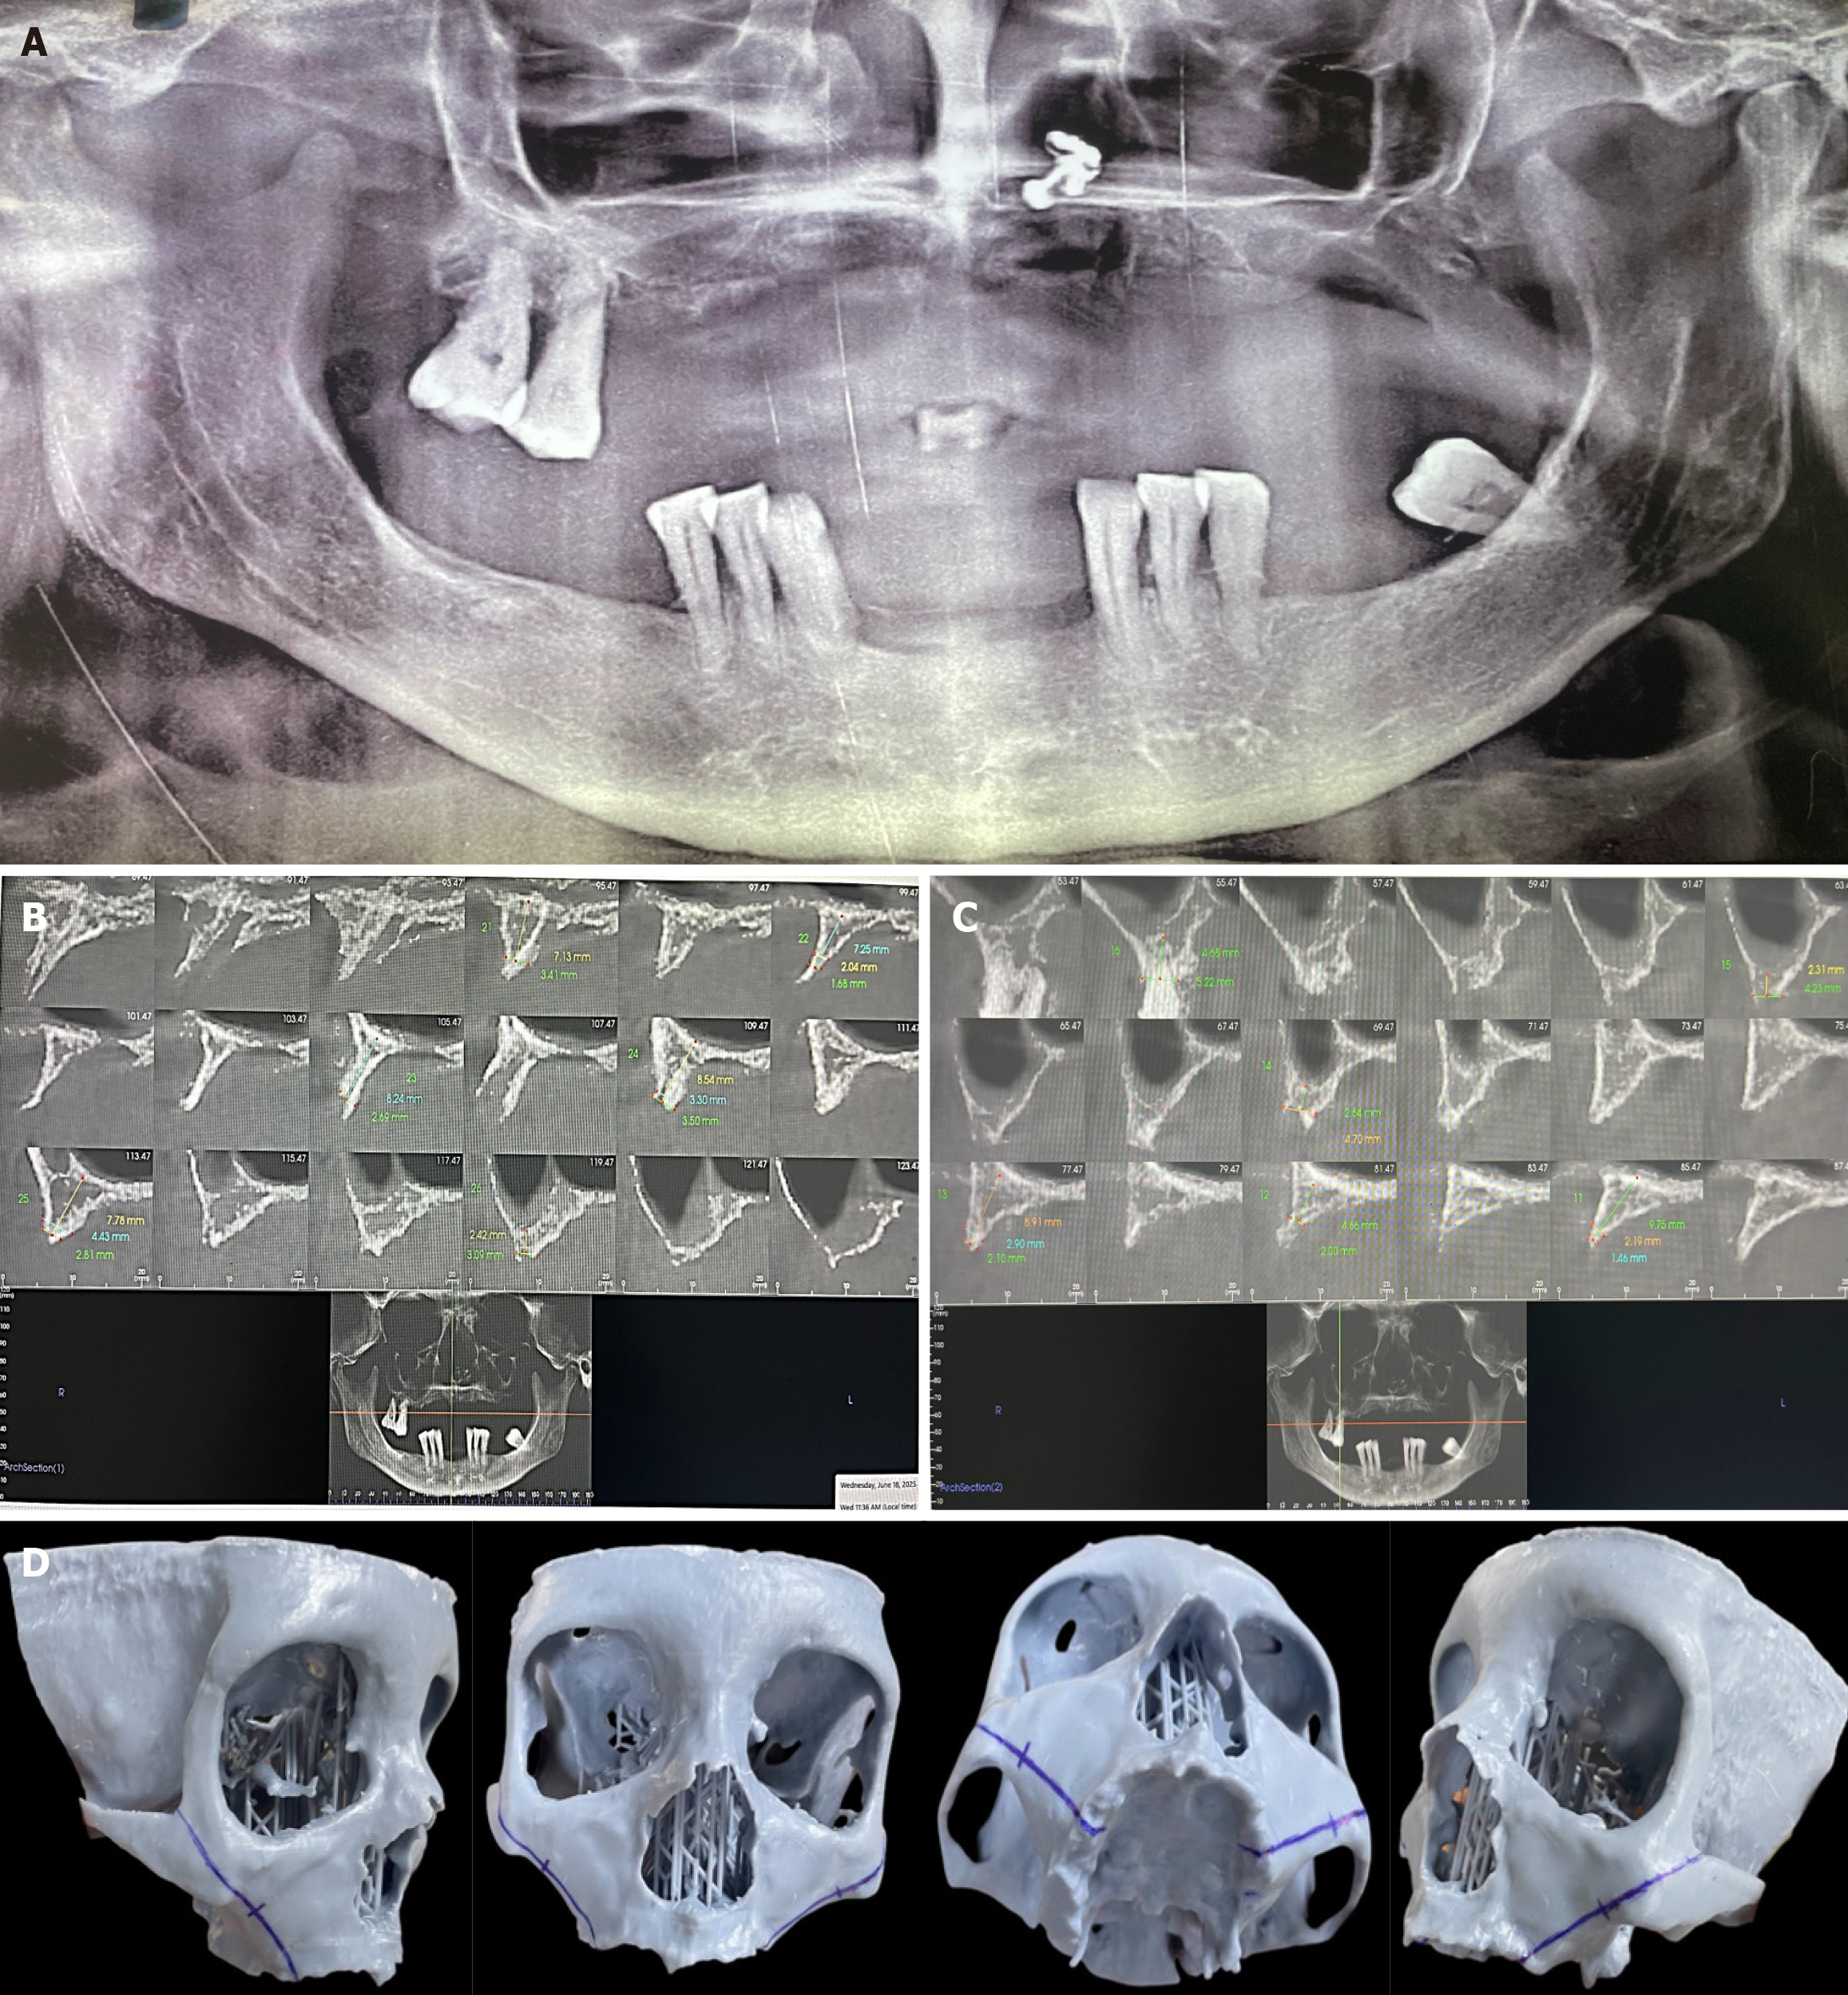

Preoperative panoramic radiography demonstrated partial edentulism with advanced alveolar ridge resorption in the posterior maxilla and marked pneumatization of the maxillary sinuses, rendering conventional implant placement unfavorable. The mandible exhibited an irregular alveolar crest morphology with reduced periodontal support around the remaining teeth (Figure 2A).

Cone-beam computed tomography (CBCT) confirmed severe maxillary atrophy, with residual vertical bone height measuring less than 4 mm in multiple posterior regions (Figure 2B and C). To facilitate precise surgical planning, a stereolithographic three-dimensional printed model was fabricated from the CBCT dataset. This model enabled detailed assessment of zygomatic bone volume, implant angulation, and proposed implant trajectories, while allowing identification of critical anatomical landmarks (Figure 2D). Based on these radiographic findings, a graftless rehabilitation strategy using posterior zygomatic implants combined with anterior nasalis implants in the maxilla, supplemented by conventional implants in the mandible, was planned.